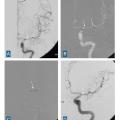

Il est capital de réaliser une imagerie artérielle dès la phase diagnostique pour planifier la suite de la prise en charge. Dans cette indication, l’angio­scanner a une meilleure sensibilité que l’angio-IRM en temps de vol pour la détection des anévrismes de taille inférieure à 3 mm. Une attention particulière est portée aux sites de développement préférentiel des anévrismes dits « de bifurcation ». (fig. 3).

L’angiographie digitale permet de planifier et de suivre le traitement lorsqu’il est réalisé par voie endovasculaire. (fig. 4)